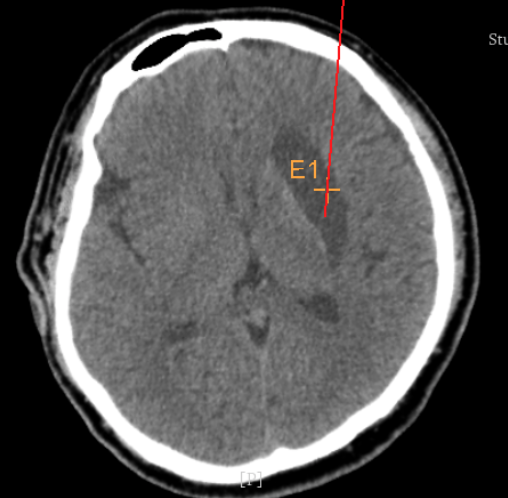

3個(gè)月前CT:腦出血